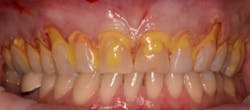

This new biological approach involving blood derivatives A-PRF and I-PRF combined with precision minimally invasive surgery for root coverage demonstrates faster healing without the need of a donor site. The morbidity of GDT is decreased and patient case acceptance is higher compared with traditional grafts. Before-and-after pictures are shown below (figures 15–22).